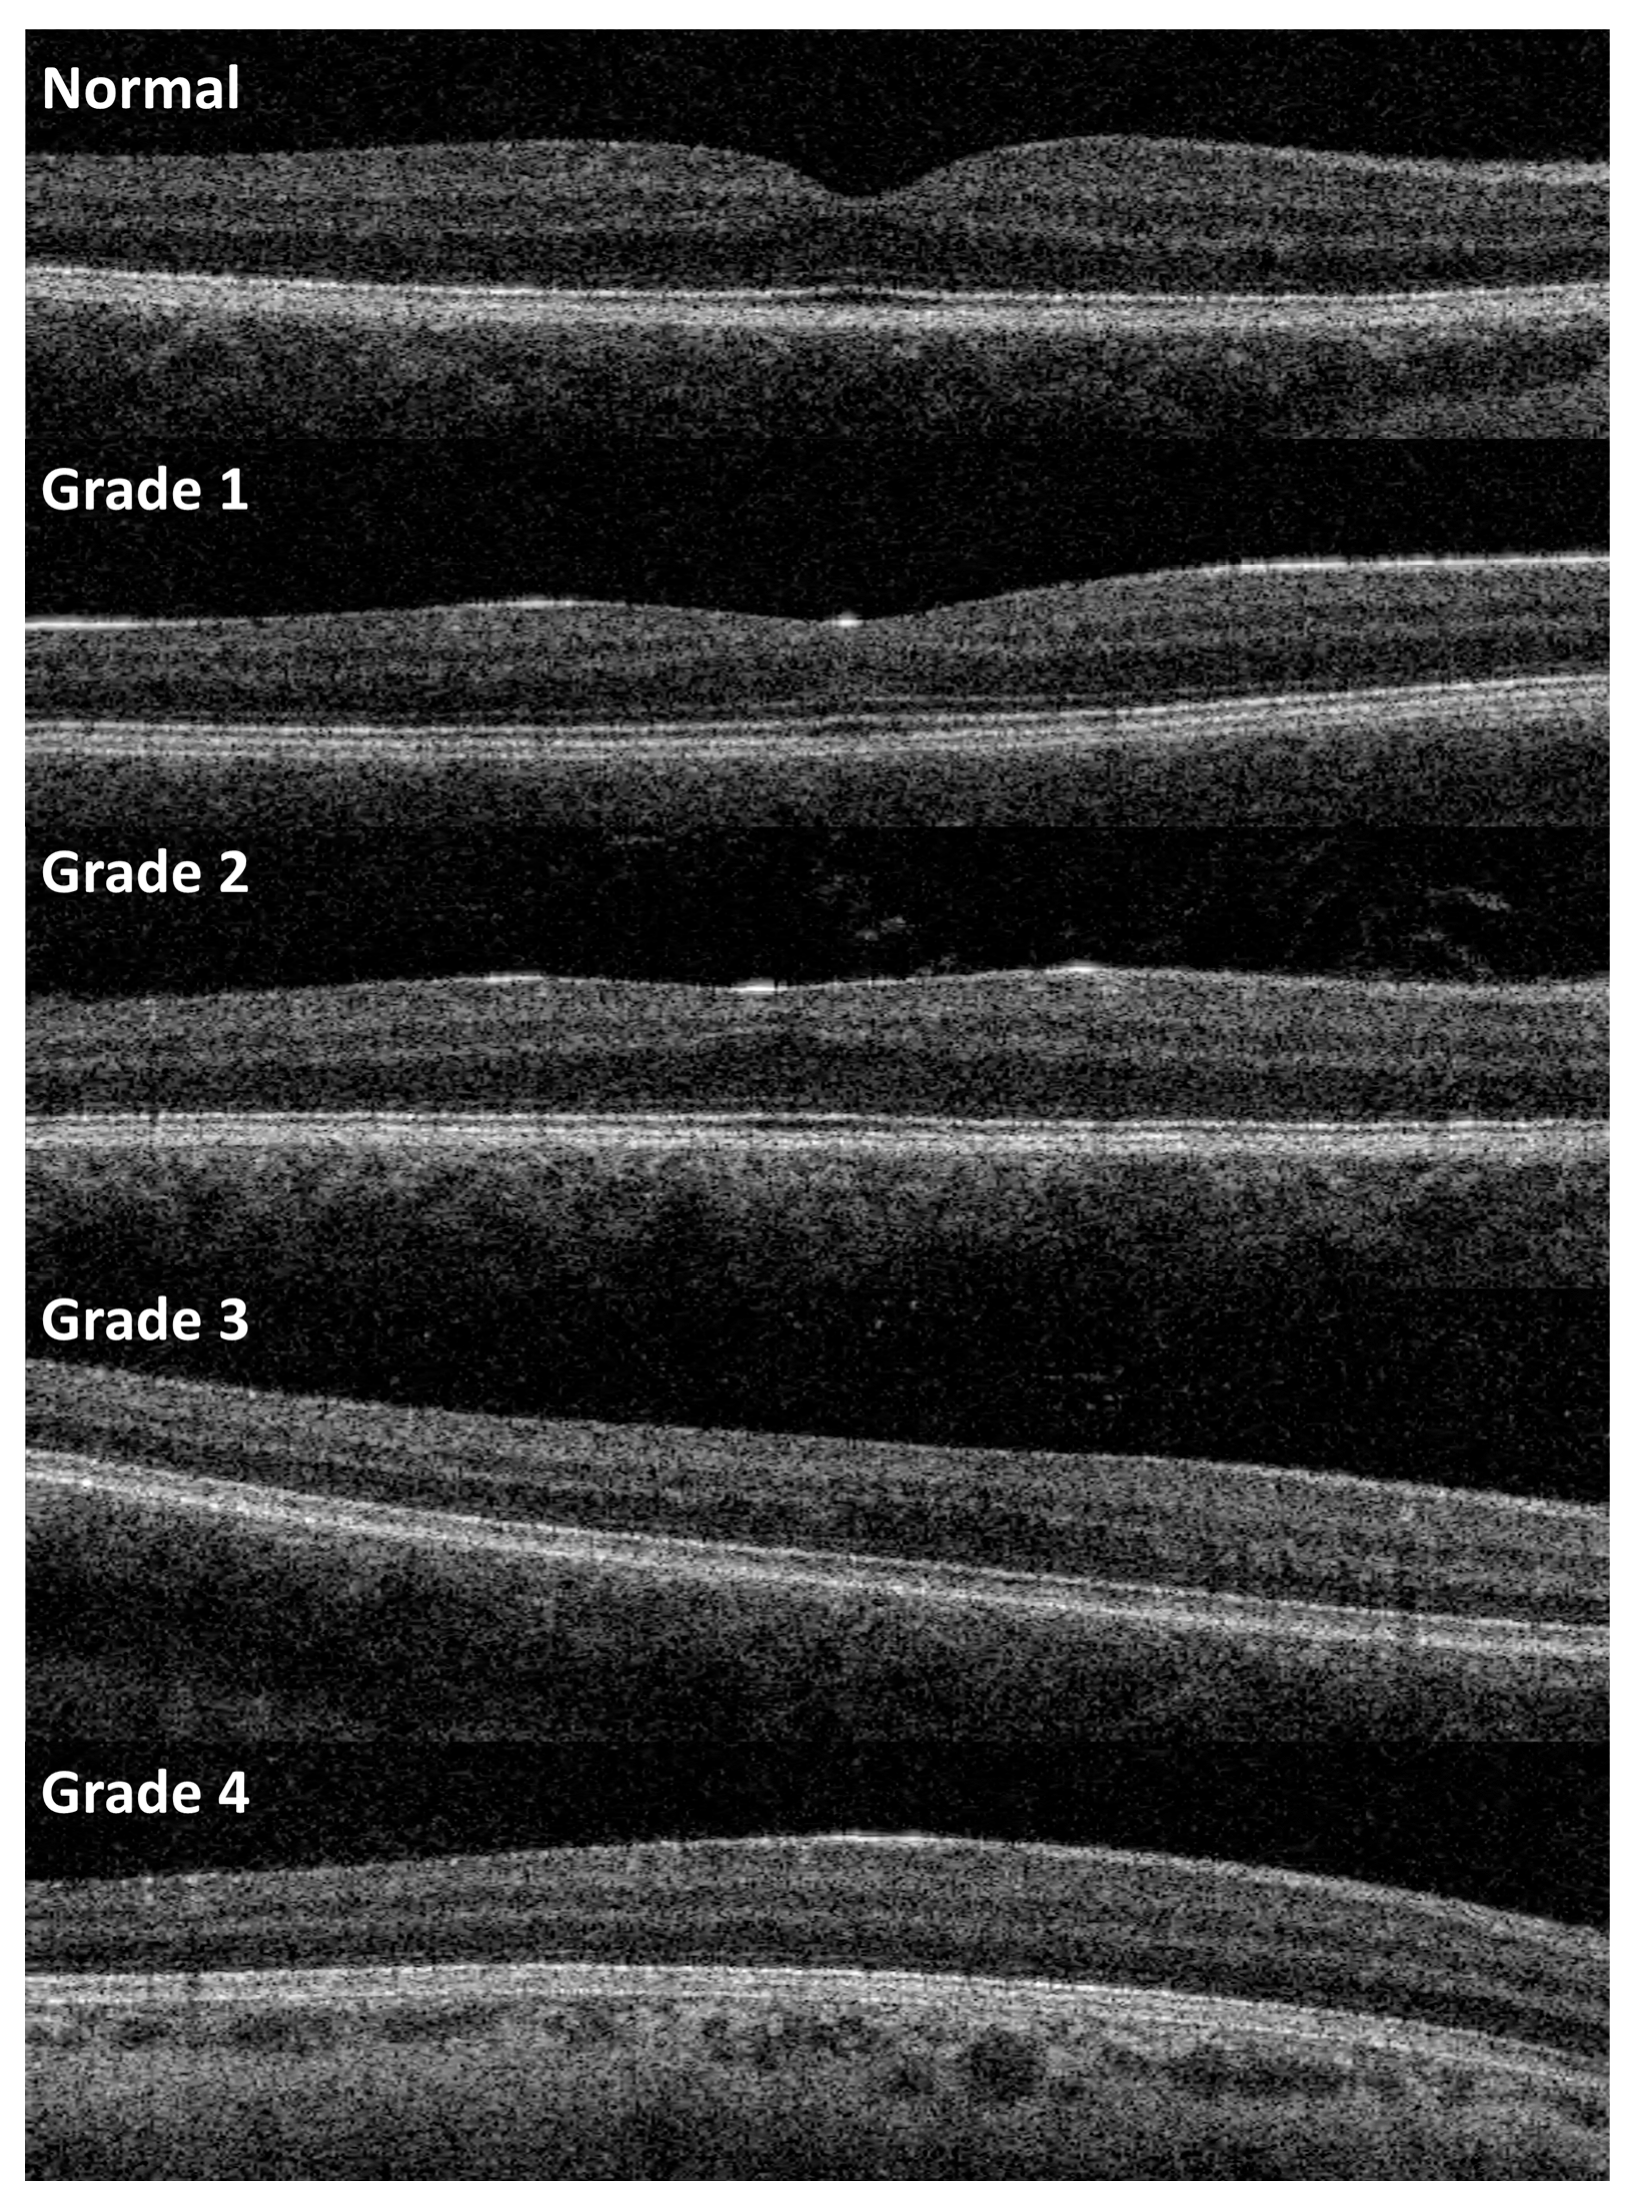

- Thomas, M.G.; Kumar, A.; Mohammad, S.; Proudlock, F.A.; Engle, E.C.; Andrews, C.; Chan, W.-M.; Thomas, S.; Gottlob, I. Structural Grading of Foveal Hypoplasia Using Spectral-Domain Optical Coherence Tomography a Predictor of Visual Acuity? Ophthalmology 2011, 118, 1653–1660. [Google Scholar] [CrossRef]

- Rufai, S.R.; Thomas, M.G.; Purohit, R.; Bunce, C.; Lee, H.; Proudlock, F.A.; Gottlob, I. Can Structural Grading of Foveal Hypoplasia Predict Future Vision in Infantile Nystagmus?: A Longitudinal Study. Ophthalmology 2020, 127, 492–500. [Google Scholar] [CrossRef]